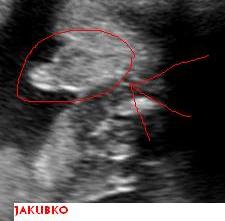

tesime sa na Jakubka🙂)